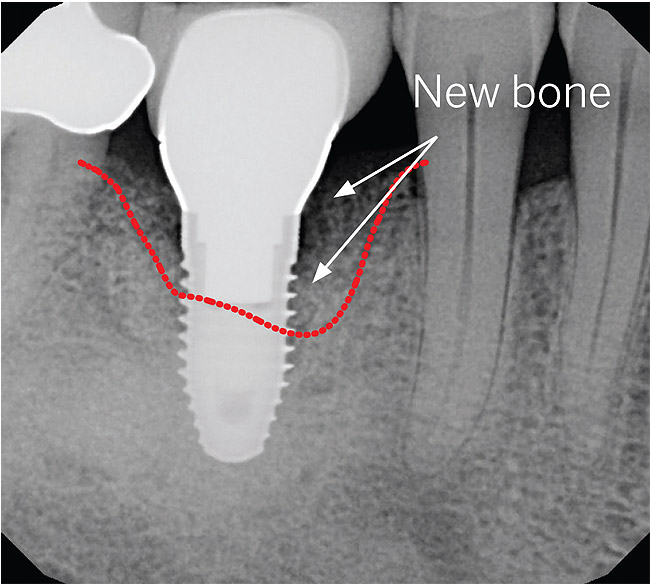

A recently published prospective case series described the technique, materials, and rationale for a protocol to successfully treat peri-implantitis with a regenerative approach.16 The results reported in the study were unique in that in addition to an average bone fill of more than 3 mm of the defect, soft-tissue levels post-surgery showed an average of more than 1 mm of coronal coverage of the implant surfaces (Figure 4 and Figure 5).

Figure 4  A pre-surgical periapical radiograph of the mandibular right peri-implantitis-affected first molar implant. (Photo reproduced with permission from the American Academy of Periodontology.) (Reference: Froum SJ. Regenerative treatment for peri-implantitis affected implant: a case report. Clinical Advances in Periodontics. 2012. Figure 5  [accepted for publication])

Figure 4

Figure 5  A 7-year post-surgical periapical radiograph showing the bone fill of the defect. (Photo reproduced with permission from the American Academy of Periodontology.) (Reference: Froum SJ. Regenerative treatment for peri-implantitis affected implant: a case report. Clinical Advances in Periodontics. 2012. Figure 13. [accepted for publication])

Figure 5